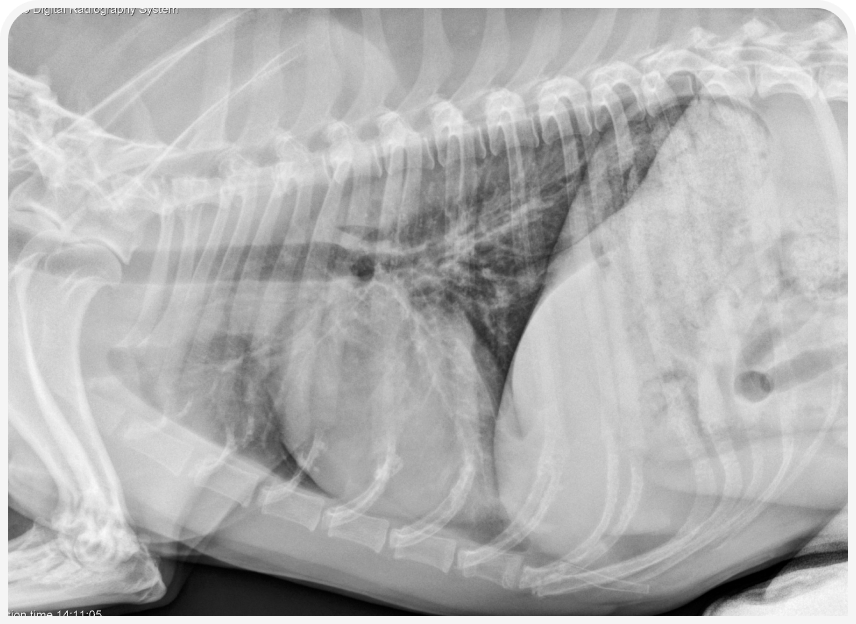

Диагностика коллапса дыхательных путей по рентгенограммам шейного отдела и грудной клетки ненадежна (8), но иногда позволяет выявить сопутствующие легочные заболевания, например пневмонию или бронхоэктазы, и заболевания сердца. Если сделать рентгенограммы в боковой проекции и на вдохе, и на выдохе, можно лучше визуализировать изменение просвета дыхательных путей: на полном вдохе можно обнаружить коллапс шейной части трахеи, а на выдохе — уменьшение размеров просвета внутригрудной части трахеи или крупных бронхов (Рисунок 1).

В целом при рентгенографии часто получают ложноположительные результаты, в то же время степень коллапса часто остается недооцененной, место коллапса удается определить не всегда, а документирование внутригрудного коллапса дыхательных путей или долевого бронхиального коллапса ненадежное.

При рентгенографии органов грудной клетки у собак с бронхитом можно выявить бронхиальный тип легочного рисунка (Рисунок 2) или увеличение количества и толщины стенок дыхательных путей, но в некоторых случаях данные рентгенографии могут оказаться относительно неинформативными.

Бронхоэктазы характеризуются расширением стенок и отсутствием нормального сужения дыхательных путей к периферии (Рисунок 3), однако рентгенография для подтверждения этого состояния относительно малочувствительна. Более чувствительна для оценки диаметра дыхательных путей компьютерная томография, позволяющая описать распространенность заболевания.